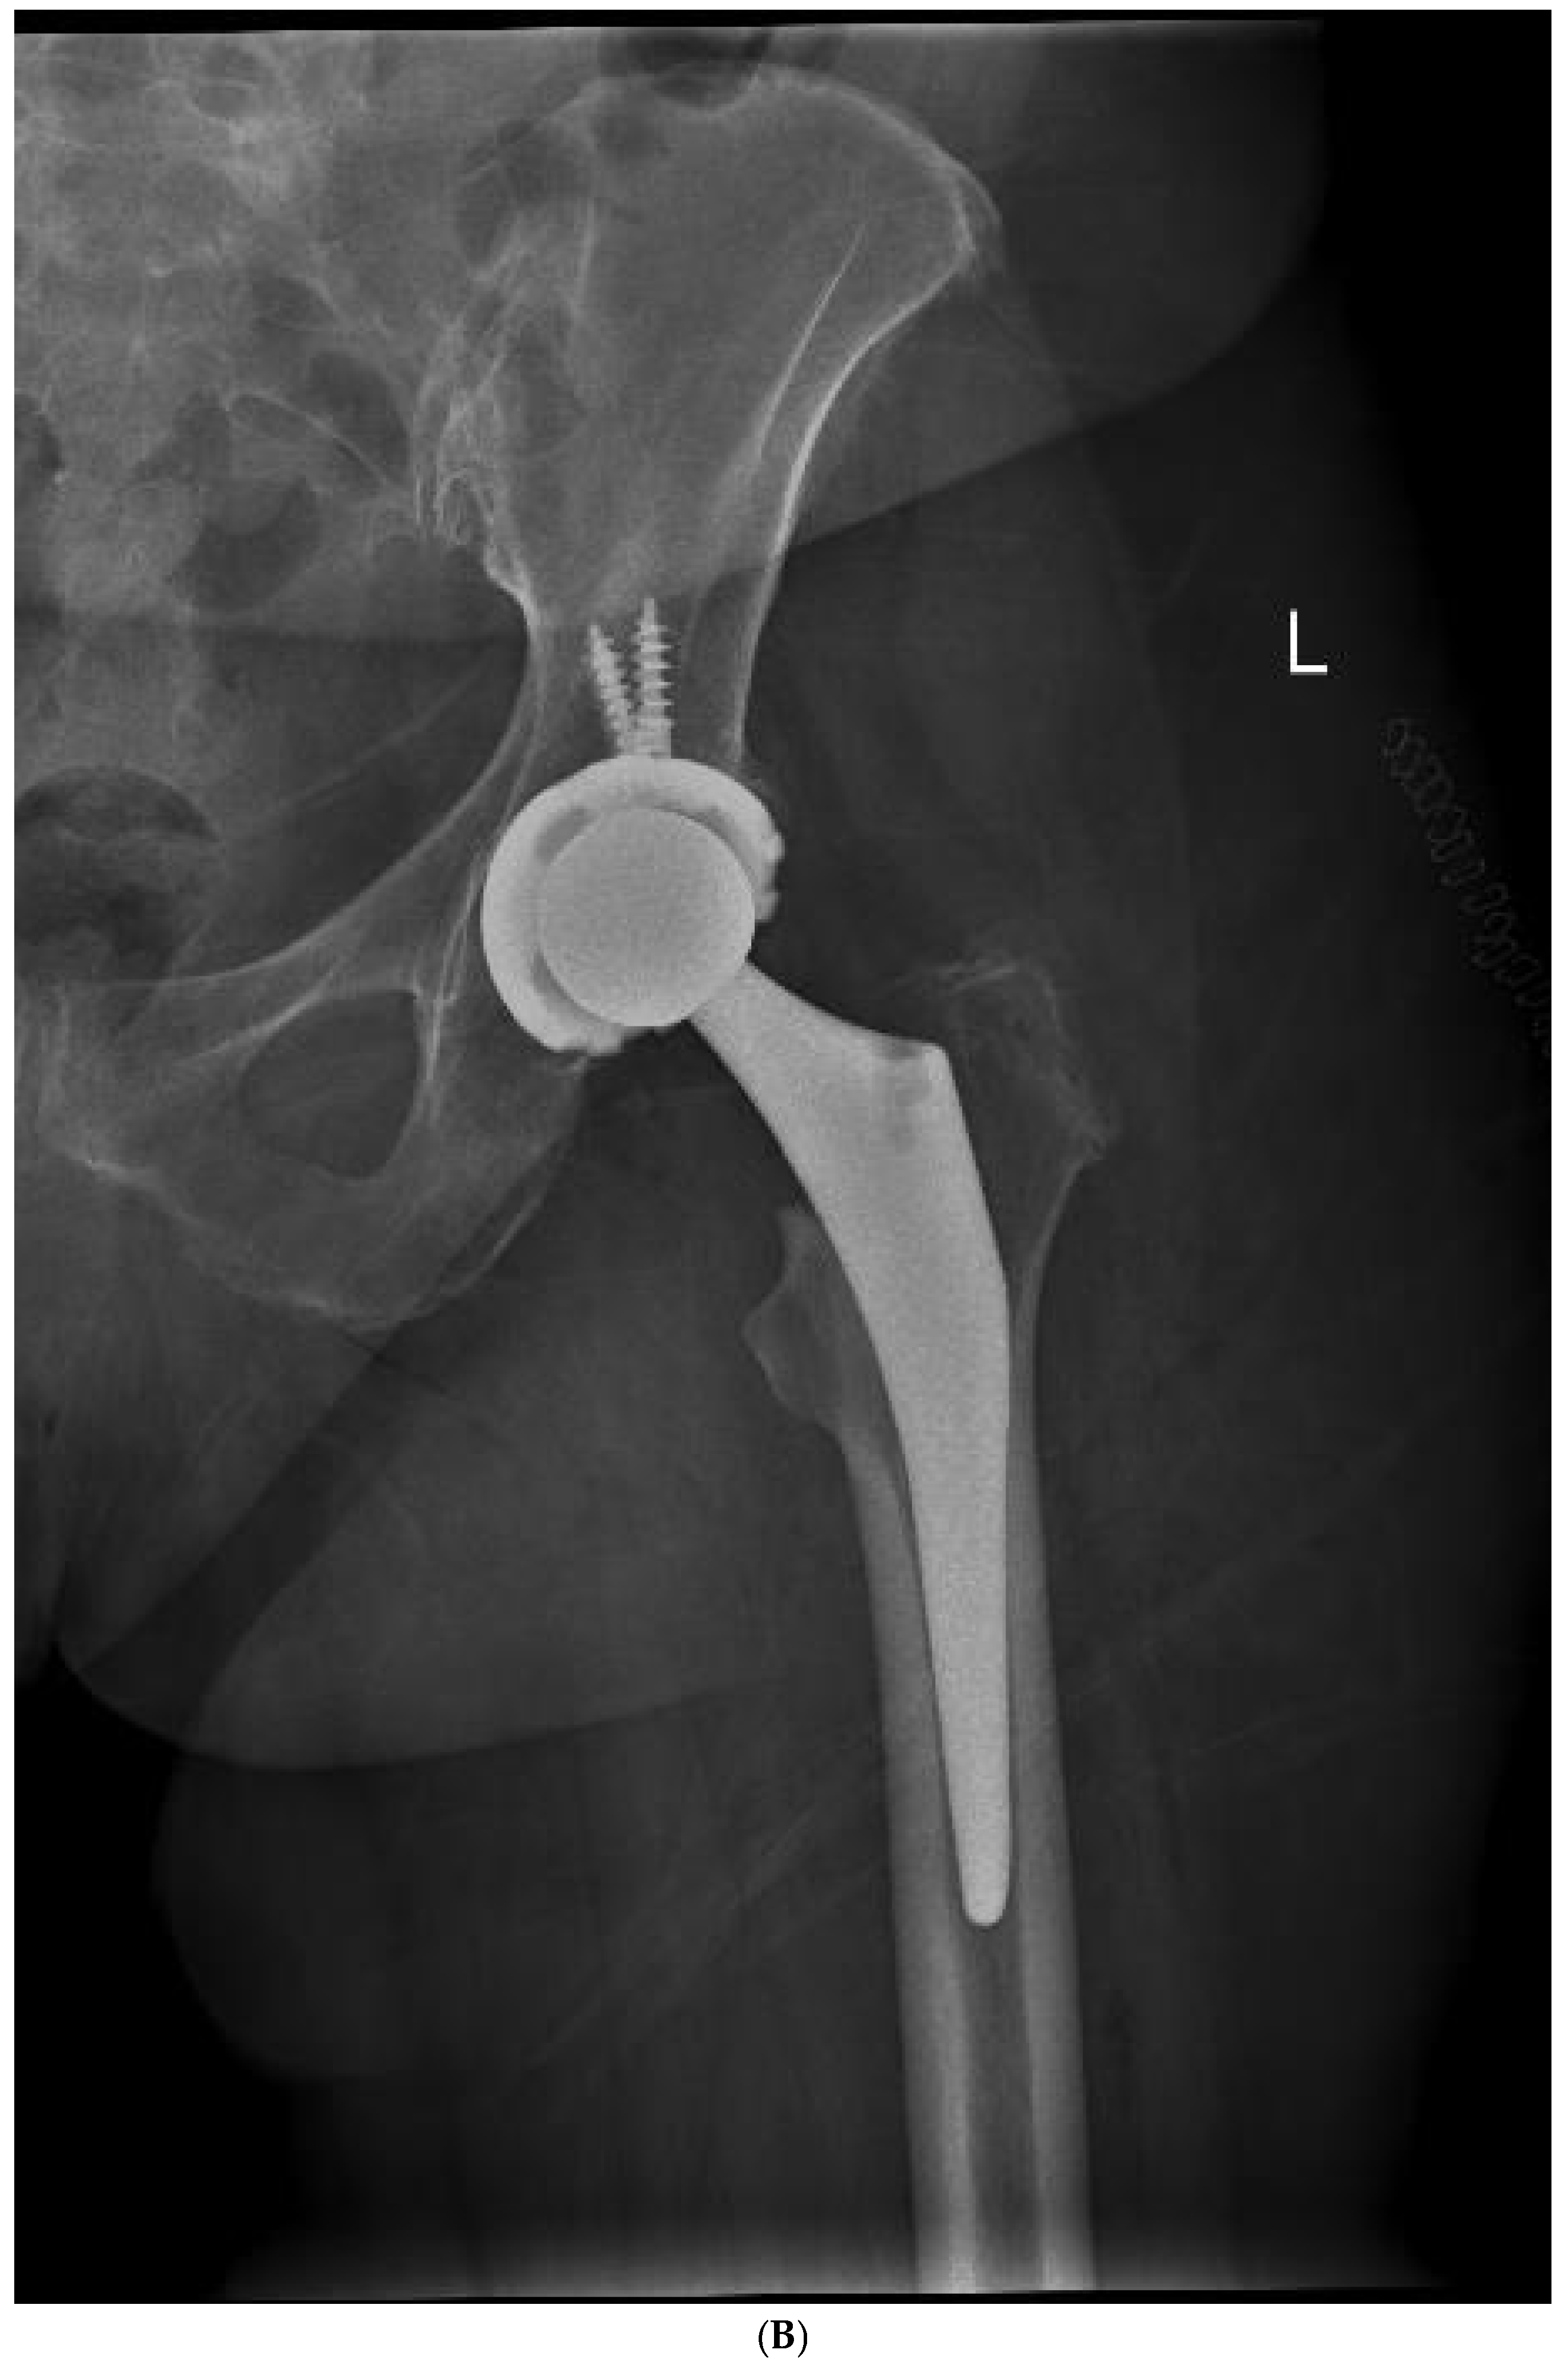

Figure 4.

(A) Preoperative anteroposterior X-ray. Left hip sustained a displaced femoral neck fracture. (B) Postoperative anteroposterior X-ray (CSS group). Femoral stem shows osseointegration and good proximal loading, with no bone resorption at final follow-up. (C) Postoperative lateral X-ray (CSS group). At final follow-up, the stem shows no subsidence and good fixation.